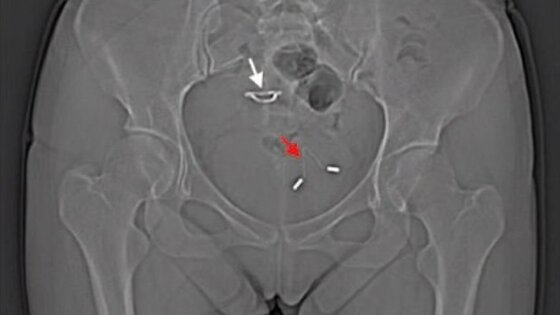

Врачи обнаружили в мочевом пузыре 26-летней женщины внутриматочную спираль через годы после того, как она забеременела и родила, несмотря на использование этого контрацептива. Женщина прибыла в больницу с жалобами на боль в животе.Китайские врачи раскрыли загадку, которая мучила длительное время 26-летнюю пациентку. Долгие годы она испытывала странную боль в животе, но не могла понять, с чем она связана. Оказалось, что еще в 2011 году девушка установила себе внутриматочную спираль, однако через несколько месяцев она забеременела, а в феврале 2012 произвела на свет ребенка. Малыш появился благодаря кесареву сечению, и врачи при этом не обнаружили никакого следа внутриматочной спирали. Они предположили, что каким-то образом она сохранилась в матке. Но рентгеновский снимок тазовой области позволил ответить на вопрос, каким образом девушка забеременела, несмотря на использование контрацептива. Оказалось, что спираль перфорировала матку и проложила себе путь прямо в мочевой пузырь, что и вызвало осложнение, связанное с мочевыводящими путями.Описывая этот случай в одном из научных журналов, врачи подчеркивают, что перфорация матки является одним из самых странных осложнений, которые можно только представить при использовании внутриматочных спиралей. Это осложнение наблюдается у одной женщины из каждой тысячи, устанавливающих спирали. Однако поскольку далеко не всегда это сопровождается какими-либо симптомами, то на самом деле число столкнувшихся с данным осложнением может быть даже ещё выше. На способность вызывать подобные осложнения влияет целый ряд факторов, включая разновидность использованной спирали, а также время ее установки и квалификацию врача.Когда спираль прокладывает себе путь внутрь тела, она может проникнуть довольно глубоко. После перфорирования матки спираль могут обнаружить даже в брюшной полости, как подчеркивают ученые.